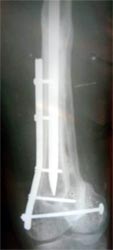

病例三、患者42岁,股骨中1/3骨折骨不连2年,钢板手术失败,明显畸形。

采用上述方法成功治愈。